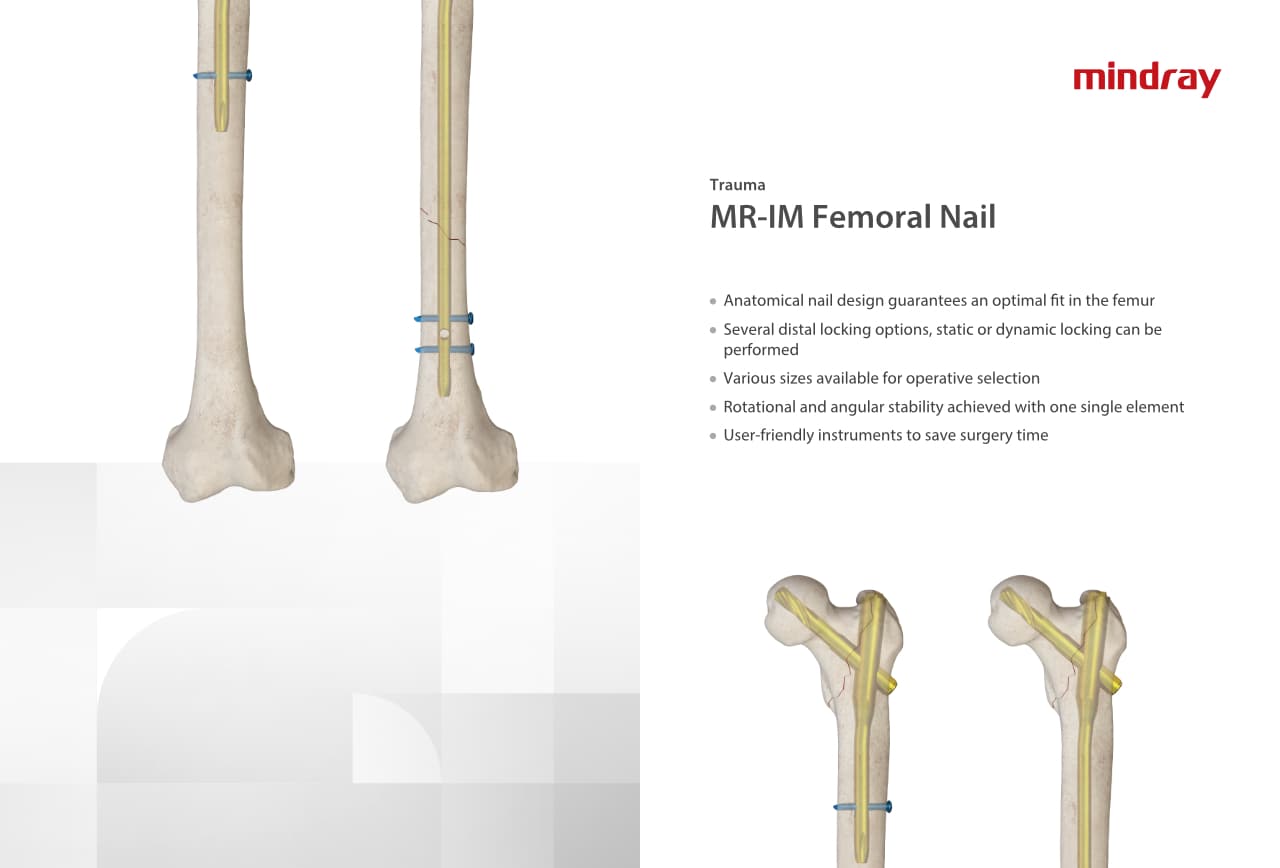

–Ю—А—В–Њ–њ–µ–і–Є—З–µ—Б–Ї–Њ–µ –њ–Њ–і—А–∞–Ј–і–µ–ї–µ–љ–Є–µ –Ї–Њ–Љ–њ–∞–љ–Є–Є Mindray, —А–∞—Б–њ–Њ–ї–Њ–ґ–µ–љ–љ–Њ–µ –≤ –£—Е–∞–љ–µ, —П–≤–ї—П–µ—В—Б—П –Њ–і–љ–Є–Љ –Є–Ј –≤–µ–і—Г—Й–Є—Е –њ—А–Њ–Є–Ј–≤–Њ–і–Є—В–µ–ї–µ–є –Њ—А—В–Њ–њ–µ–і–Є—З–µ—Б–Ї–Њ–є –њ—А–Њ–і—Г–Ї—Ж–Є–Є –Є–Ј –Ъ–Є—В–∞—П. –Ю–љ–Њ –Ј–∞–љ–Є–Љ–∞–µ—В—Б—П –Є—Б—Б–ї–µ–і–Њ–≤–∞–љ–Є—П–Љ–Є –Є —А–∞–Ј—А–∞–±–Њ—В–Ї–Њ–є, –њ—А–Њ–Є–Ј–≤–Њ–і—Б—В–≤–Њ–Љ –Є –Љ–∞—А–Ї–µ—В–Є–љ–≥–Њ–Љ —В—А–∞–≤–Љ–∞—В–Њ–ї–Њ–≥–Є—З–µ—Б–Ї–Є—Е –Є —Б–њ–Є–љ–∞–ї—М–љ—Л—Е –Є–Ј–і–µ–ї–Є–є, –њ—А–Њ–і—Г–Ї—Ж–Є–Є –і–ї—П –∞—А—В—А–Њ–њ–ї–∞—Б—В–Є–Ї–Є –Є –і—А—Г–≥–Є—Е —Е–Є—А—Г—А–≥–Є—З–µ—Б–Ї–Є—Е –Є–Ј–і–µ–ї–Є–є. –° –Љ–Њ–Љ–µ–љ—В–∞ —Б–≤–Њ–µ–≥–Њ –Њ—Б–љ–Њ–≤–∞–љ–Є—П –≤ 1999 –≥–Њ–і—Г –Љ—Л —Г—Б–њ–µ—И–љ–Њ –њ—А–Њ—И–ї–Є —Б–µ—А—В–Є—Д–Є–Ї–∞—Ж–Є—О ISO 9001, ISO 13485 –Є CE, –≤—Л–і–∞–љ–љ—Г—О T?V –Є —Н–Ї—Б–њ–Њ—А—В–Є—А—Г–µ–Љ –њ—А–Њ–і—Г–Ї—Ж–Є—О –≤ –±–Њ–ї–µ–µ —З–µ–Љ 50 —Б—В—А–∞–љ –њ–Њ –≤—Б–µ–Љ—Г –Љ–Є—А—Г.